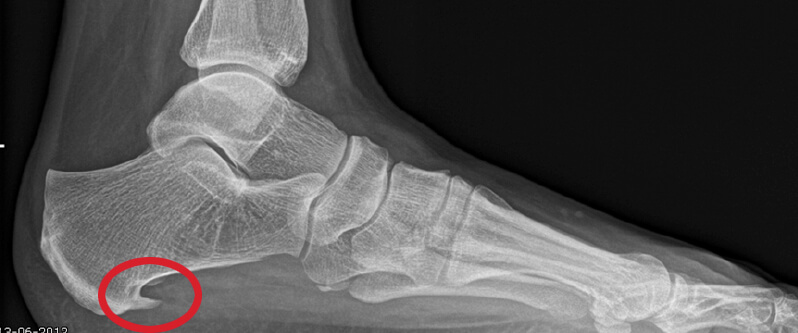

Een hielspoor is een verkalking aan de onderkant van het hielbot (calcaneus). Deze zit bij de aanhechting van de peesplaat die naar de voorvoet loopt. Een hielspoor is waarneembaar op röntgenfoto, maar ook is hij goed te zien op een echo.

De hielspoor hoeft niet altijd pijn te doen, zolang deze geen ontsteking veroorzaakt. Als men 100 mensen van de straat haalt en bij deze mensen gaat onderzoeken op hielspoor, zullen 30 mensen een hielspoor hebben waar ze geen weet van hebben. De pijn die mensen hebben met hielspoor komt omdat de hielspoor een ontsteking in de peesplaat veroorzaakt.

Deze oorzaken hebben alles te maken met het feit dat op de peesplaat een langdurige druk wordt uitgeoefend. Als gevolg hiervan zal het lichaam reageren en ontstaat er een vergroeiing van het van het bot (verkalking) aan het hielbot, waar de peesplaat is aangehecht. De pijn die u kunt voelen heeft te maken met een ontsteking die de hielspoor kan veroorzaken in de peesplaat. De hielspoor zelf doet geen pijn.